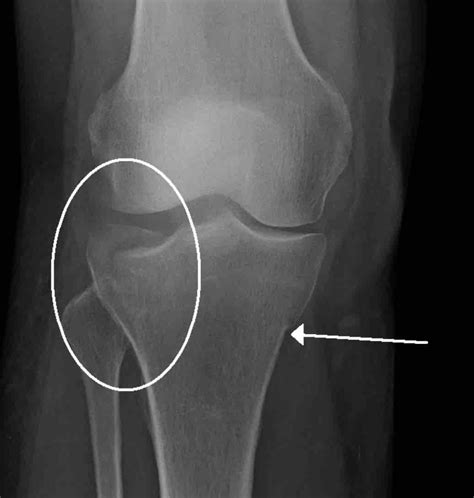

Diagnosis and Clinical Assessment

If you suspect you have a stress fracture, it is vital to seek professional medical advice. A healthcare provider will typically perform a physical examination, assessing the site of tenderness and your range of motion. Because stress fractures are often so small, they do not always appear on standard X-rays, especially in the first few weeks of the injury.

Doctors may suggest more sensitive imaging techniques if clinical symptoms remain high despite a clear X-ray. An MRI is often considered the "gold standard" for diagnosing a stress fracture tibia because it can detect bone marrow edema (swelling inside the bone), which is an early sign of stress-related injury before a fracture line even forms.